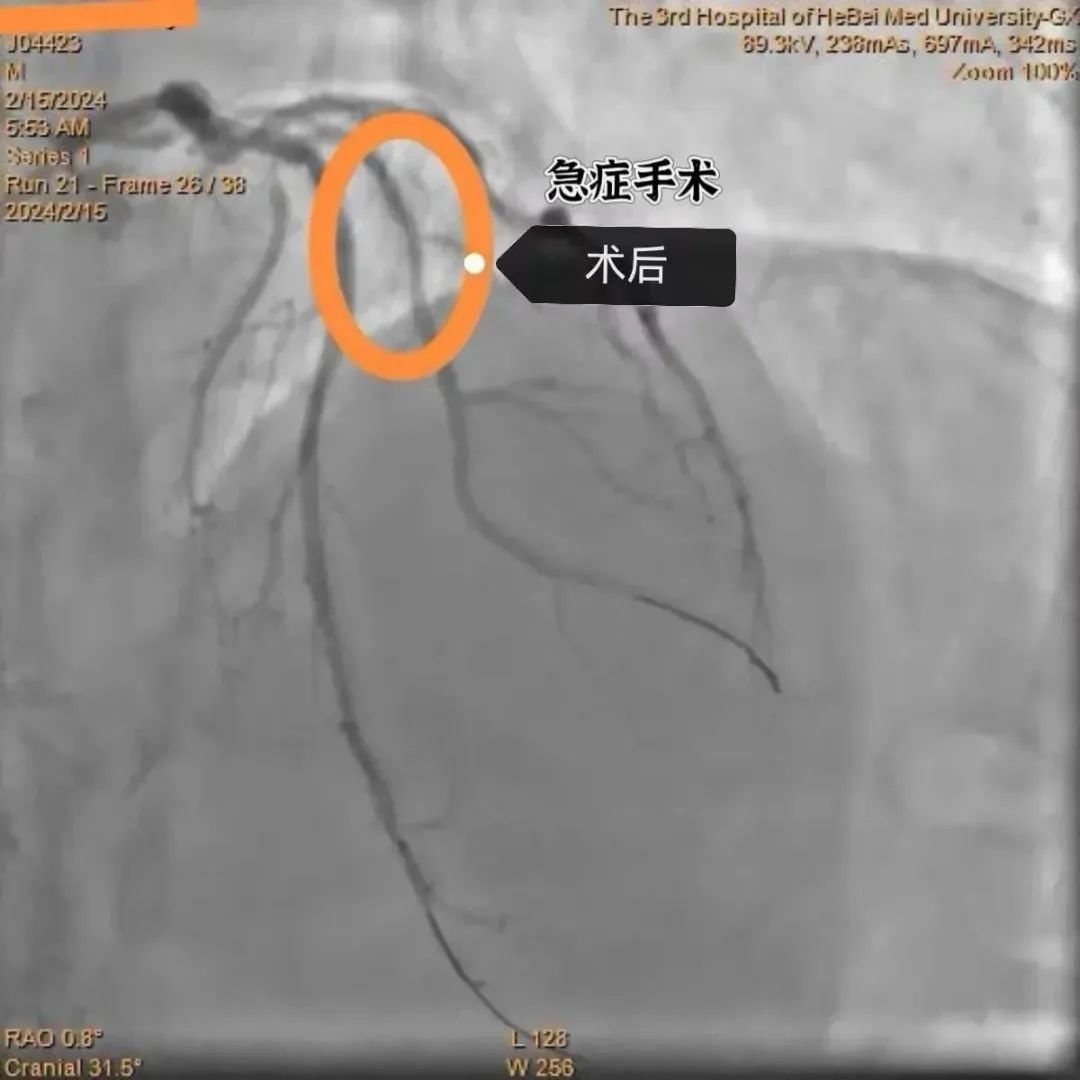

术中冠脉造影结果显示,患者的大对角支近段闭塞,而且开口被曾经放置的支架覆盖,手术难度较大。面对挑战,殷洪山主任凭借丰富的经验和精湛的技术,沉着应对,精准操作,经过一个多小时的努力,顺利开通闭塞血管,患者转危为安。